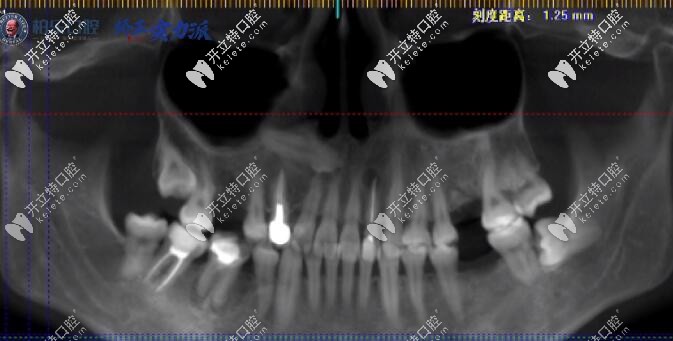

【南寧柏樂口腔門牙反頜矯正前后對比病例】:

南寧柏樂口腔門牙反頜矯正前后對比<span style=

矯正方案:隱形牙齒矯正19個月

矯正醫(yī)生:董瑜

顧客反饋:我在柏樂做了隱形矯正,對于這次的正畸效 果很不錯,總體算下來,就是覺得價格高了些,其它都很滿意。